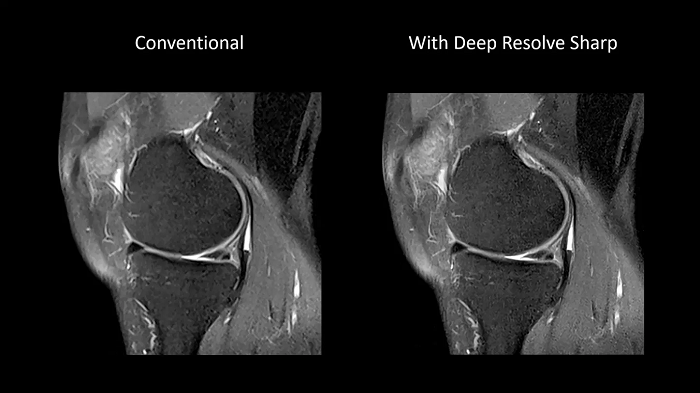

Deep Resolve Sharp

Using a convolutional neural network of TSE sequences, Deep Resolve Sharp produces high-resolution images from low-resolution input. Sharper and crisper images can be achieved without compromising on data acquisition time.

80 cm bore MAGNETOM Free.Max

Image Courtesy: University Hospital Erlangen, Germany | Image-ID: 4aaaa0459